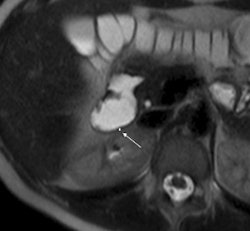

| 1.5-tesla MR images show a portion of the duodenum wall in a patient with untreated celiac disease (above), a patient with treated celiac disease (below), and a healthy patient (bottom). The images show no significant differences in duodenal wall thickness (arrow). |

Their analysis found that a mean maximum enhancement of the duodenal wall was 229.1 ± 46.4 in untreated patients with celiac disease, 109.8 ± 27.8 in treated patients with celiac disease, and 94.7 ± 17.9 in control subjects.

The researchers also found that duodenal wall thickness did not significantly differ between patients with celiac disease who were not treated for the condition, patients with celiac disease who were treated, and healthy control subjects.